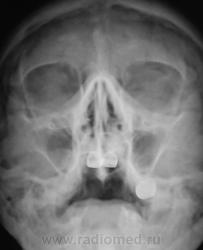

Пациент направлен на рентгенографию придаточных полостей носа отоларингологом.

Гипоплазия лобных, снижена прозрачность решетчатого лабиринта, киста? справа в верхнечелюстной на фоне хр.гайморита.

Основная пазуха также затенена, в левой гайморовой пазухе тоже есть пристеночные затенения. Похоже на кисту в правой г/п. А почему хронический?!

1. Хорошо, не будем утверждать, что это киста.

2. Скиалогически имеем ОДНУ однородную тень с округлым контуром, ПЛАВНО (без острого угла) переходящую на латеральную стенку.

3. Утверждение о выходе ЗА ПРЕДЕЛЫ пазухи, как по мне, не имеет под собой достаточной аргументации.

4. ПРОСВЕТЛЕНИЕ под тенью есть и с противоположной стороны, хоть и выражено в меньшей степени (вспомните о симптоме Рейнберга).